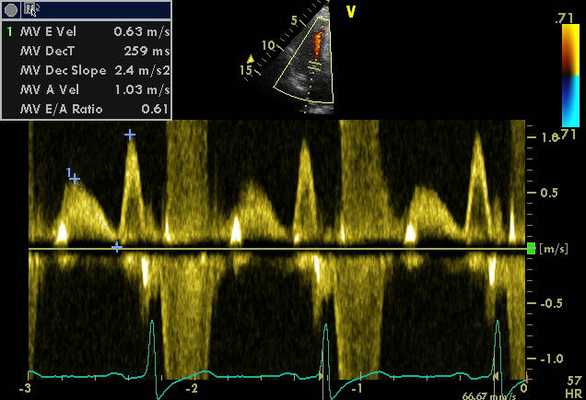

Фетальная аритмия. Показаны два преждевременных сокращения предсердий (стрелки), за которыми следуют два преждевременных сокращения желудочков (звездочки).

- М-эхокардиография - позволяет наблюдать интракардиальные структуры (стенки камер сердца, створки клапанов) в режиме движения, оценивать систолическую функцию желудочков.

- Допплерэхокардиография - используется для изучения гемодинамики в сосудах и камерах сердца, а также оценки сердечного ритма. Проводится в режиме ЦДК и импульсной допплерографии.